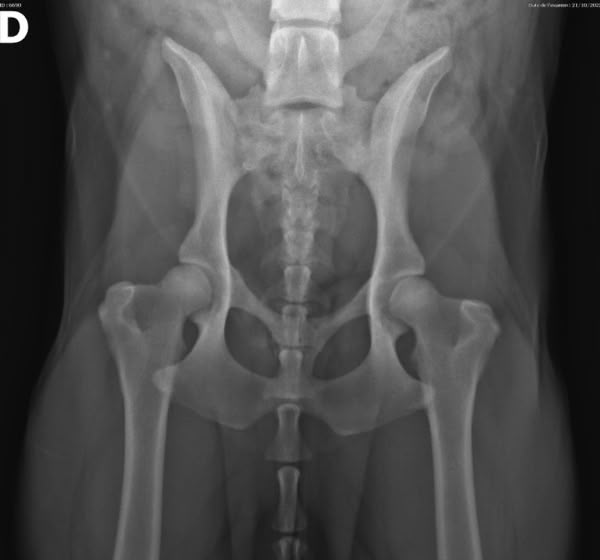

Le dernier cas de notre étude est un chat présenté pour ataxie et dont le scanner montre une fracture ponctiforme de l'os pariétal gauche du crâne avec abcès intracrânien et sous-cutané, probablement secondaires à un traumatisme. Un traitement médical est mis en place. Après une amélioration transitoire de son état général, le patient décède trois jours plus tard.